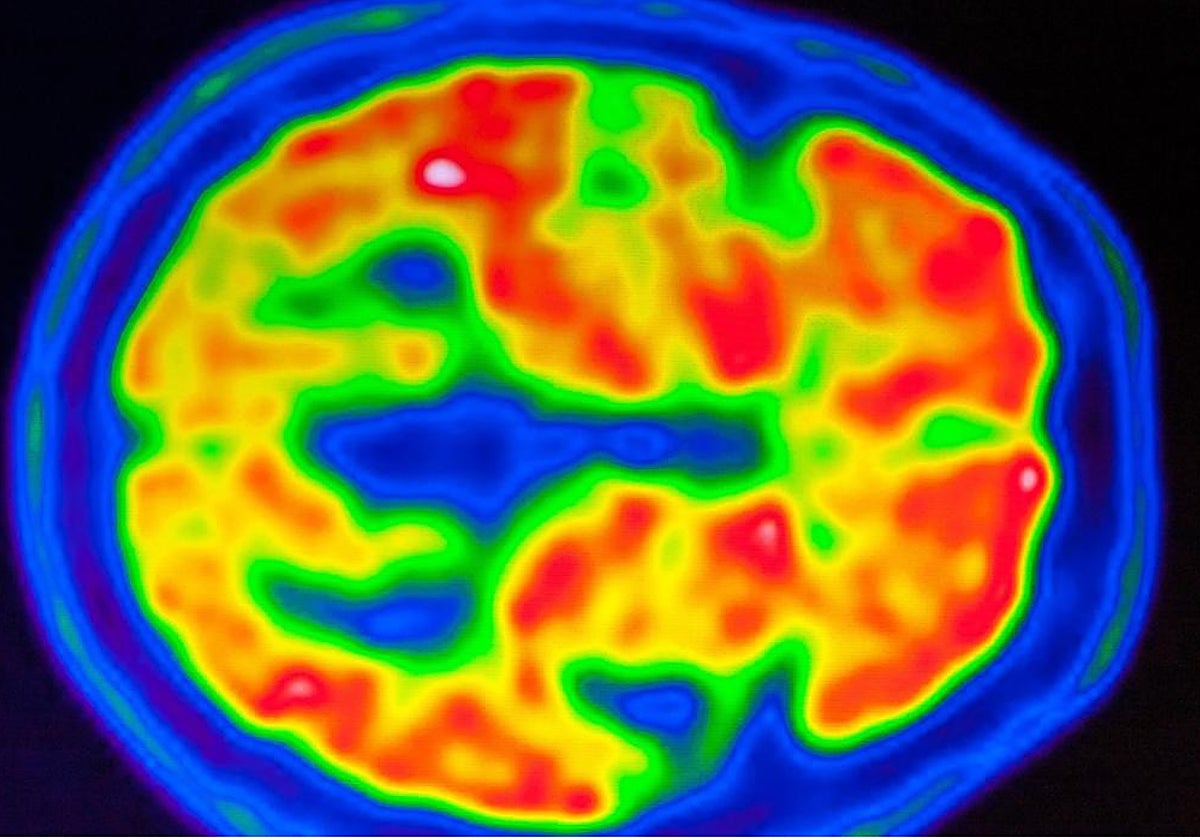

Junto a eso, los estudios de resonancia magnética ayudan a conocer qué focos se ven más afectados, prosigue el neurólogo: «En la actualidad es muy importante la medición de la presencia de las proteínas Tau y de beta-amiloide en el cerebro. Ahora podemos detectar su presencia de forma temprana tanto en el líquido cefalorraquídeo como por técnicas de medicina nuclear a través de PET-TC en centros altamente especializados como el nuestro».